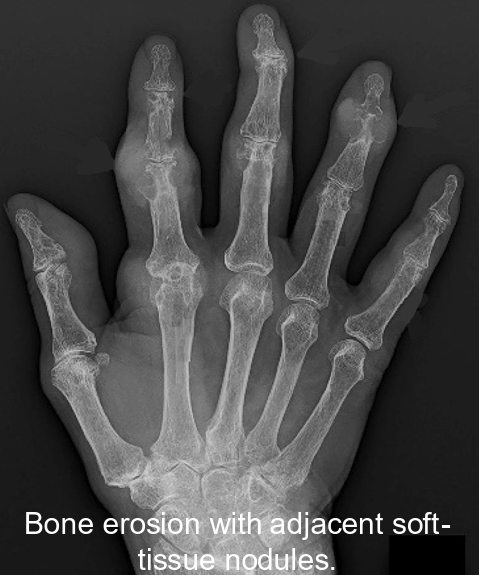

Gout

(definiton + pathogenesis + diagnosis + treatment)

Accumulation of sodium-urae crystals within joints

Pathogenesis: Hyperuricaemia causing deposition of monosodium-urate crystals in the joints. Flare ups caused by immune response to urate crystals

Genes involved: SLC2A9 (for GLUT2 receptors), IL-37

Diagnosis:

Sudden onset of excruciating pain within the joint (often metatarsophalangeal)

Advanced gout: recurrent flare with persistent joint pain

Gold standard: presence of MSU crustals in synovial fluid taken from joint aspiration during flare

Serum urate >0.42mmol/L

Imaging via x-ray, ultrasound, CT shows urate crystals